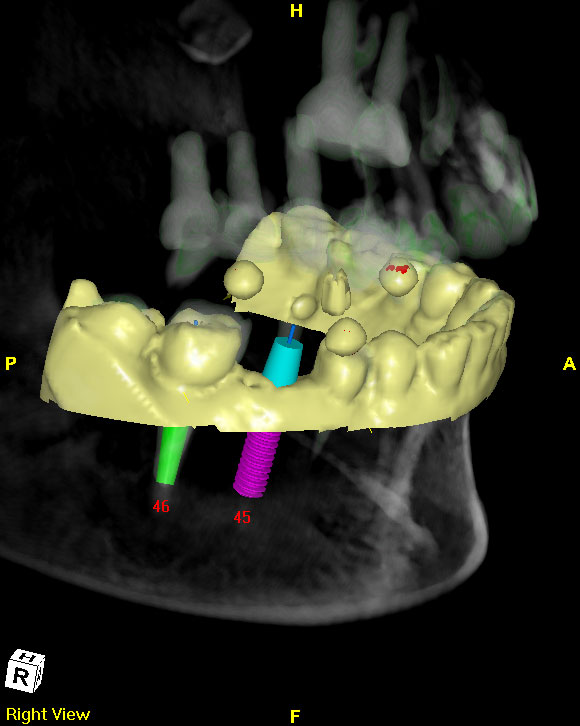

手術導板/

微創手術

近年來植牙技術已經廣泛運用在口腔重建治療,對於傳統局部或全口活動義齒使用上仍不滿意的病患,利用植牙治療也常常能得到滿意的治療結果,植牙臨床經驗和操作的熟悉度是影響植牙成敗的主要因素,透過植牙導航系統可降低經驗值所造成的誤差,如能再有效調整上穎植入時之手勢與位置,加強操作熟練度,必更能提升其精準度上的落差。這種微創手術不僅造成的傷口較小且恢復速度快,也可有效減少傳統植牙方式可能造成的錯位或傷及神經的情況。(圖60-62)